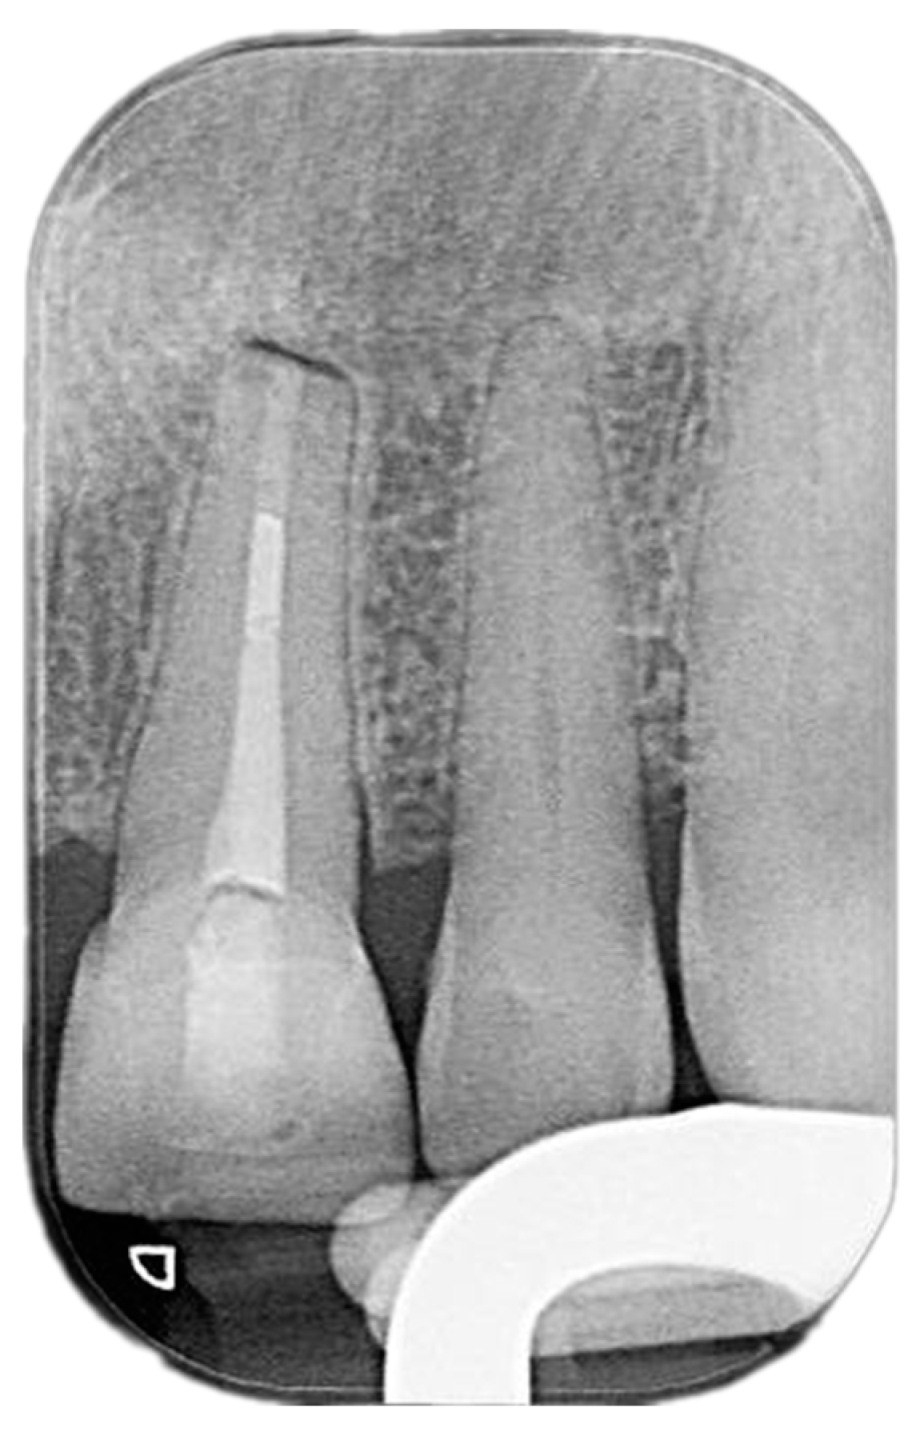

2. Case Presentation

2.1. Chief Complaints History and Clinical Findings

2.2. Delivery of Treatment

2.4. Healing of the Defect and Follow Up